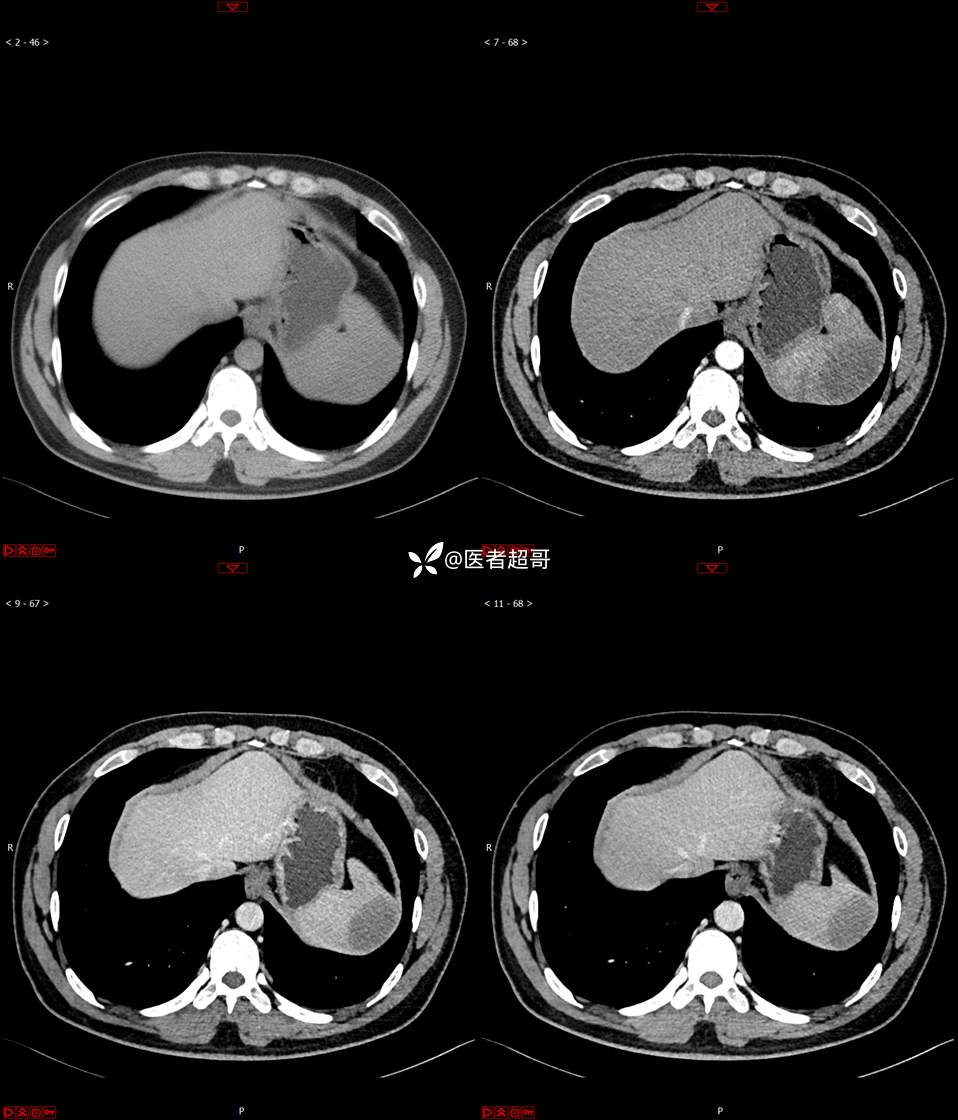

【影诊笔记738】脾脏低密度影,请诊断分析~~

男,33岁 0201215 01

主 诉:发现脾占位2月余。

现病史:患者2月余前体检行肝胆胰脾肾彩超提示脾占位性病变,未予特殊诊治,1天前于区人民医院行肝胆胰脾MR平扫提示脾脏占位性病变,左肾小囊肿,现患者无腹胀、腹泻,无恶心呕吐,无胸闷憋气等症状,今为求进一步治疗,患者来我院就诊,门诊以“脾占位性病变”收入院。患者自发病以来,一般情况可,神志清,精神可,饮食、二便正常,睡眠可,体重体力无明显改变。